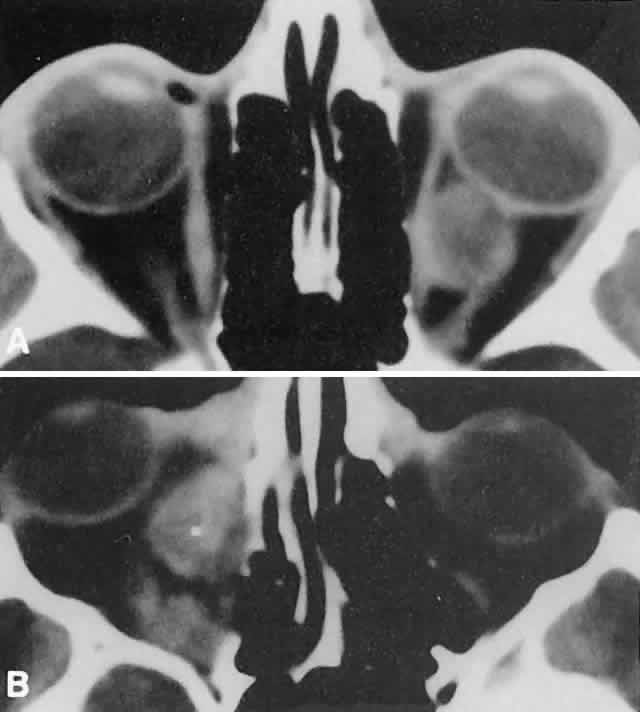

the superior nasal quadrant, with downward and outward displacement

of the globe. CT scans show the topography of the orbital mass (Fig. 1A), as well as the possible extension into adjacent bone, paranasal sinuses, or

the intracranial cavity. The circumscription that may be noted

on CT is relative, because the lesion is not encapsulated and microscopically

infiltrates normal tissue. Echography shows internal echoes of

low-to-medium amplitude. Because the cellular tumor absorbs acoustic

energy, the amplitude of the spikes falls off somewhat through the lesion (see Fig. 1B and C). MRI can help define the tumor's relationship to extraocular muscles (Fig. 2).  Fig. 1. A. Proptosis and downward, outward globe displacement developed over 2 days

in a 3-year-old girl. A homogeneous mass fills the superomedial orbit. B. Contact B-scanning shows a relatively well-circumscribed mass with uniform

internal echoes. C. Contact A-scanning shows the internal reflectivity to be of low to medium

amplitude, consistent with a sarcomatous lesion. Biopsy results confirmed

the diagnosis of rhabdomyosarcoma. Fig. 1. A. Proptosis and downward, outward globe displacement developed over 2 days

in a 3-year-old girl. A homogeneous mass fills the superomedial orbit. B. Contact B-scanning shows a relatively well-circumscribed mass with uniform

internal echoes. C. Contact A-scanning shows the internal reflectivity to be of low to medium

amplitude, consistent with a sarcomatous lesion. Biopsy results confirmed

the diagnosis of rhabdomyosarcoma.

Fig. 2. MRI shows an intraconal tumor of lower intensity than the medial rectus

muscle. The proximal muscle is splayed rather than compressed, suggesting

that the lesion originated within the medial rectus. The diagnosis

was alveolar rhabdomyosarcoma. Fig. 2. MRI shows an intraconal tumor of lower intensity than the medial rectus

muscle. The proximal muscle is splayed rather than compressed, suggesting

that the lesion originated within the medial rectus. The diagnosis

was alveolar rhabdomyosarcoma.